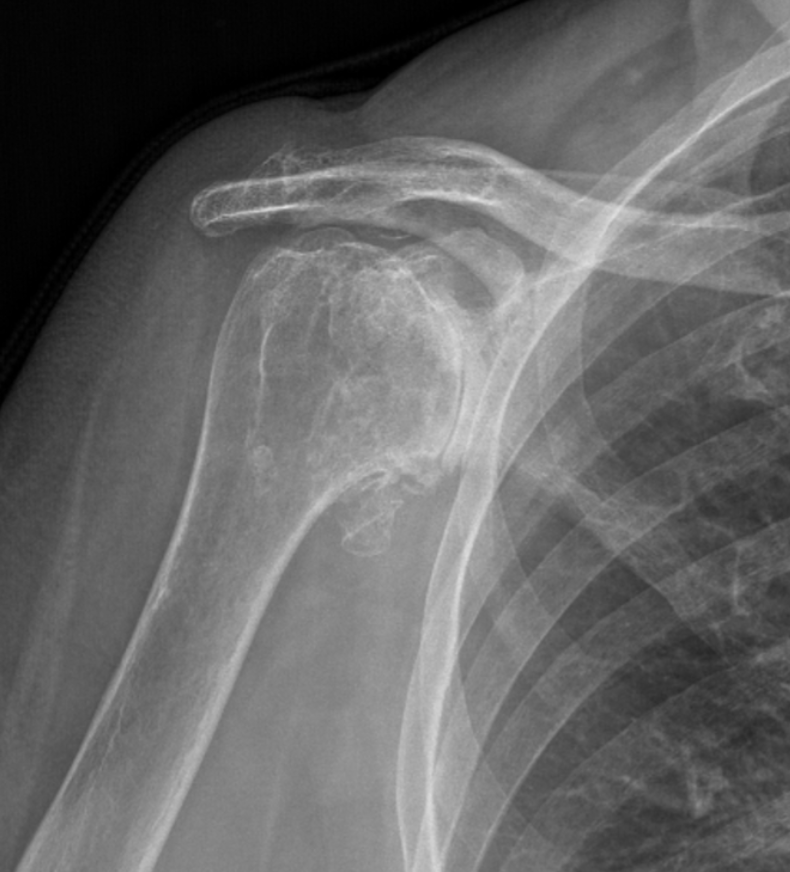

X-ray image of a shoulder showing a broken clavicle with possible shoulder dislocation.